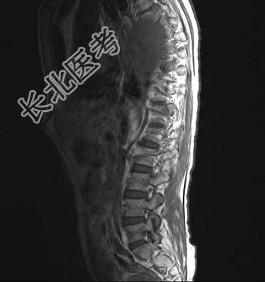

- 多项选择题常见的椎管内肿瘤(如图所示)有 ( )

A、脊膜瘤

B、胶质瘤

C、血管瘤

D、上皮样囊肿

E、神经鞘瘤